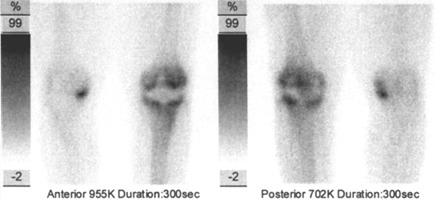

Celotělovou scintigrafii (v přední a zadní projekci) a statické pozdní scintigramy (pozdní kostní fáze) jsme provedli na stejné kameře E.CAM firmy Siemens za 2,5 hod. po aplikaci (statické scintigramy - délka akvizice 5 minut – současně v přední a zadní projekci a další akvizice současně obě boční projekce). Je výrazně zvýšená depozice radiofarmaka opět jak kolem femorální, tak kolem tibiální komponenty TEP. Dále je patrné ložisko zvýšené depozice radioindikátoru v mediálním kondylu pravé

tibie.

Tedy současně se zvýšenou perfuzí v oblasti celého pravého kolena a v mediálním kondylu pravé tibie je výrazně zvýšená osteoblastická aktivita kolem femorální a tibiální komponenty TEP i v mediálním kondylu pravé tibie

(obr.3, 4).

/ Obr. č. 3: Třífázová scintigrafie skeletu – 3., pozdní kostní fáze. Statická scintigrafie skeletu kolenních kloubů, přilehlých částí bérců a stehenních kostí 2,5 hodiny po aplikaci radiofarmaka

99mTc-oxidronátu v přední a zadní projekci /